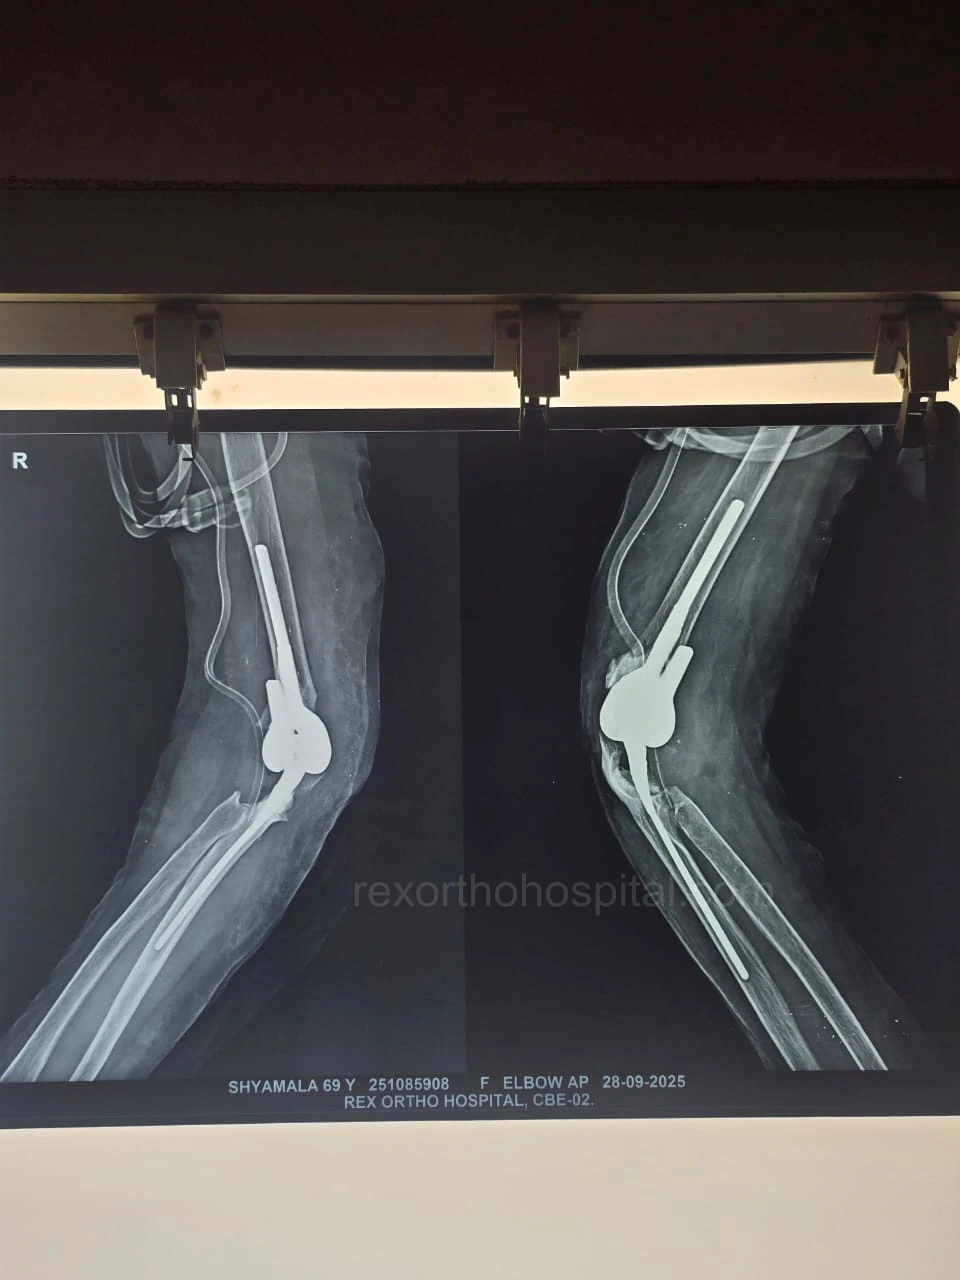

Elbow stiffness treatment aims to restore smooth movement and reduce pain caused by injury, arthritis, or long-term immobility. Our approach improves flexibility and helps regain everyday function.

From diagnosis to surgery and recovery, our team ensures you receive expert treatment and individual attention throughout your treatment journey